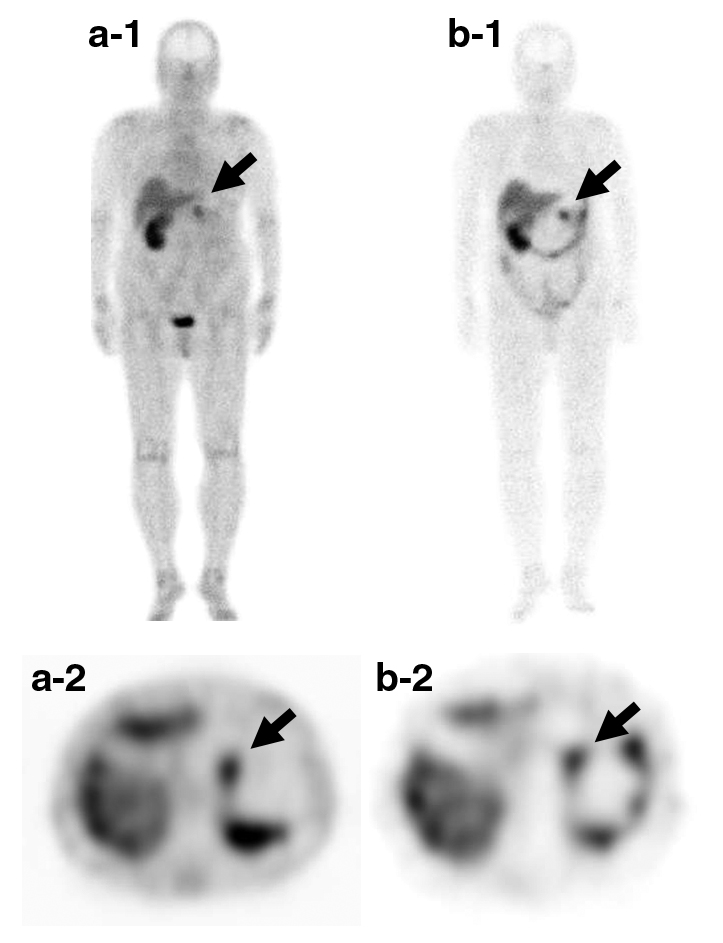

ソマトスタチン受容体シンチグラフィ所見:膵体部の腫瘤に一致し4時間後相,24時間後相で集積を認めた(Fig. 4).転移を疑う異常集積は認めなかった.

Somatostatin receptor scintigraphy. a-1, a-2: after 4 hours-phase. b-1, b-2: after 24 hours-phase. Accumulation was observed in the pancreatic body after a 4 hour- and 24-hour phase.